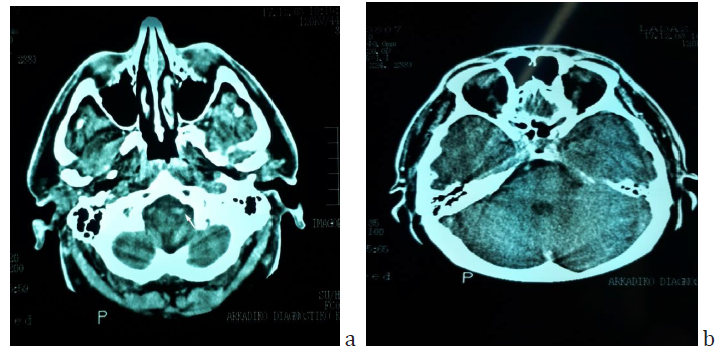

Figure 2: Brain CT scan of the patient sixteen years before the first episode of SSNHL, when he had a car accident. a) The enlargement and beginning tortuosity of the left vertebral artery is evident (arrow). b) The basilar artery has already a lateralized position at the right border of the dorsum sellae but it does not appear enlarged.

Sixteen years before the first episode, the patient had had a car accident for which he had a brain CT scan which was otherwise normal apart from an incidental comment about the existence of a tortuous left vertebral artery (Figure 2). MRI imaging findings of the vertebrobasilar segment are shown on Figures 3 & 4.

One of the unique features of the present study is the existence of an imaging modality sixteen years before the occurrence of SSNHL. Although it is not an MRI but a CT, the finding of a tortuous left vertebral artery had been pinpointed even at that time of the past. The basilar artery appeared lateralized at the level of upper pons but no ectasia was apparent yet at that time. In none of the relevant studies has there been a previous imaging report to testify the longevity and/or the pathogenesis of VBD. The asymmetric vertebral artery flow contributes to the development of basilar artery curvature in the side opposite to the side of VA dominancy. There are references about the existence of a dominant vertebral artery more frequently on the left side [18-20]. Despite the fact that hyperlipidemia and hypertension were present in the patient’s recent medical history, (of a few years) the lateralization of the BA being evident many years earlier (Figure 2b) is in accordance with the pathogenetic theory of a mechanism other than atherogenesis, involving a disfunction of matrix metalloproteinases leading to aberrant vascular remodeling and abnormal connective tissue in the arterial wall [3,22].